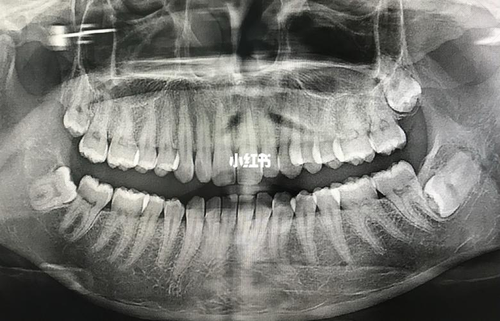

智齿是牙列最后面的牙齿,也叫第三磨牙。多数情况下在成年后萌出,因此而名为智慧齿”。由于每个人的智齿生长情况都不一样,有的萌出异常的智齿是需要拔除的,那么,长在最里面的智齿好拔吗?

长在最里面的智齿如果已完全萌出是比较好拔的,若尚未完全萌出在拔除时会有一定的难度。而且一般上颌最里面的智齿相对要比下颌的好拔。除此以外,还可以根据其生长的方向、牙根的数目等等来判断最里面的智齿好拔与否。

如果最里面的智齿牙根没有弯根的情况下,在拔除过程中也会比较容易一些。但如果出现弯根不仅需要切开牙龈,在拔除时还需要进行止血,这样视野难以看清楚,拔除的过程就会比较有难度。

由于最里面的下颌智齿一般齿根尖多与下颌神经管比较近,为了要避免对下颌神经产生创伤,在拔牙的过程中需要去除骨阻力、软组织阻力之后才能够将智齿完全拔除。一般在拔除智齿后会引起面部五至七天的肿胀,之后会自行消肿,在此期间除了要注意口腔卫生以外,还要按时服用消炎药。